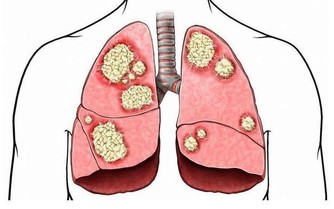

四、心臟與呼吸道1.往左側睡眠還能幫助心臟省力,改善心血管循環的健康,

躺在右側會使胸骨後的燒灼不適(火燒心)情況惡化,

側向左邊睡時大動脈的流向是往下更能有效幫助心臟向下輸送血液,

而血液流回心臟也會變的更有效率。

2.而像是有氣喘或是有呼吸中止症的人較適合側躺,因為正躺會增加呼吸的困難度。